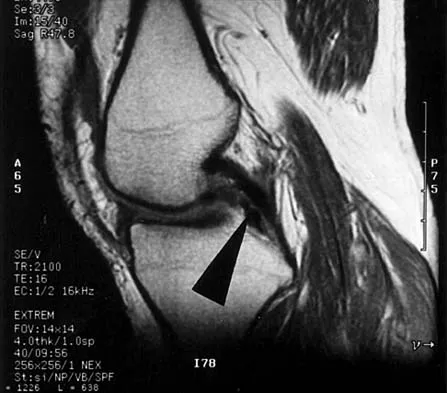

Figures 31a and 31b show the T1- and T2-weighted MRI scans of a patient's knee joint. What is the most likely diagnosis?

Explanation